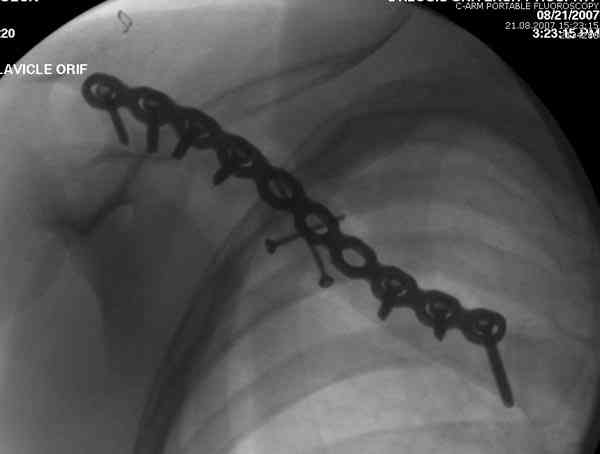

Re: Ортопедический квест: <допустимое> смещение от

Второй случай тоже недавно оперирован по поводу

ложного сустава, в марте травма, через 4.5 половиной

операция..

Djoldas Kuldjanov, MD